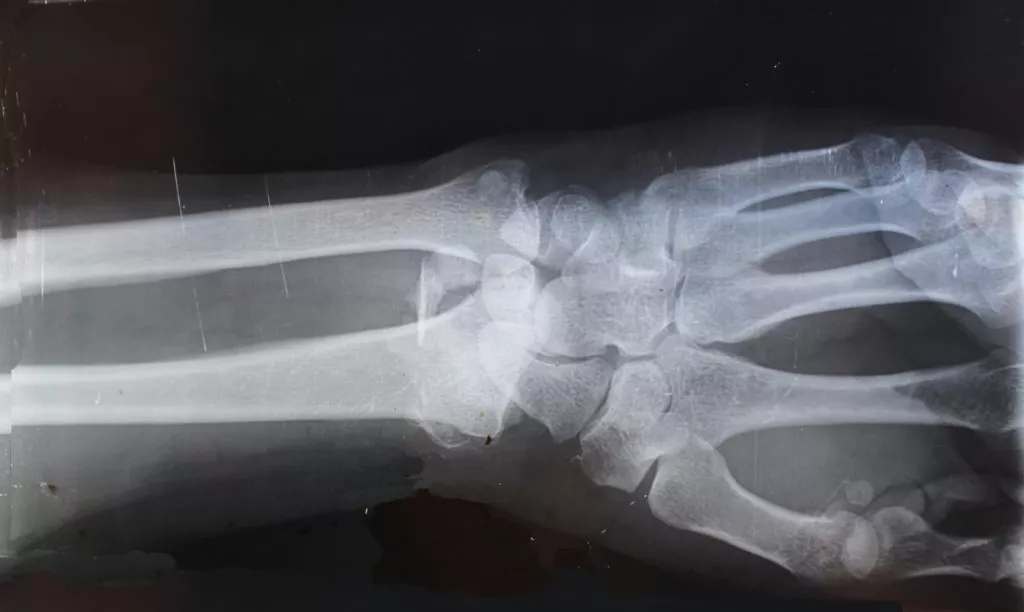

Una persona que ha sufrido una amputación traumática enfrentará costos médicos significativos durante todo el proceso de recuperación. Cirugías, medicamentos, prótesis, rehabilitación y terapia son solo algunos de los gastos que implica una amputación.